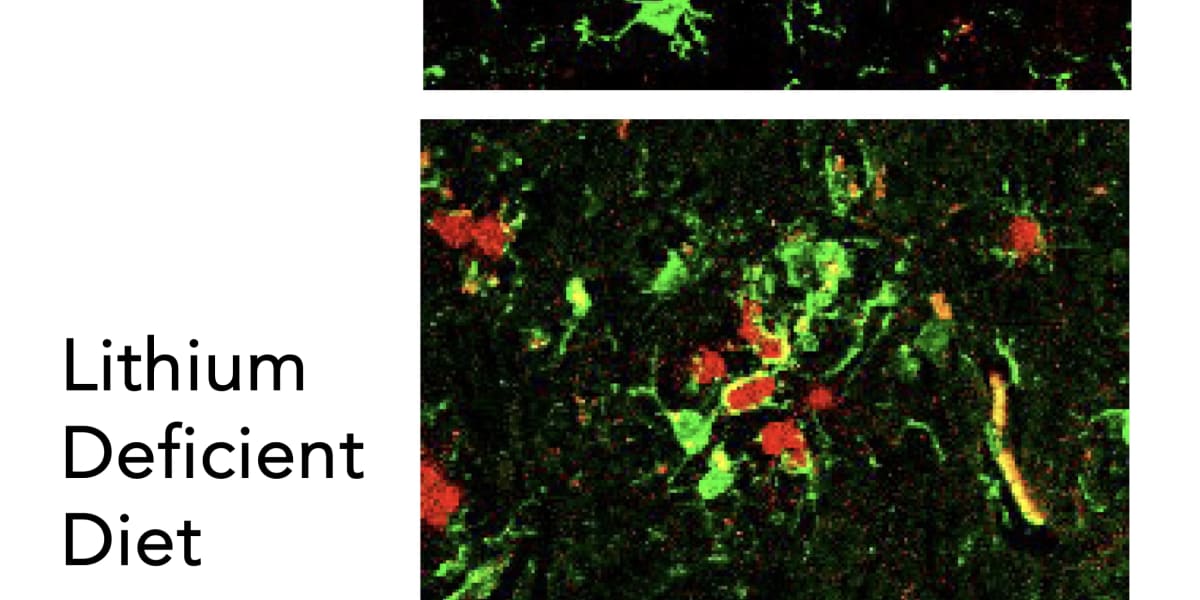

Recent studies in mice and human brain tissue suggest that loss of naturally occurring brain lithium is a potential early driver of Alzheimer’s disease (AD), leading to inflammation, amyloid plaques, neurofibrillary tangles, and accelerated memory decline.

In experiments, restoring lithium levels through supplements reversed these neurological and cognitive deficits in mice.